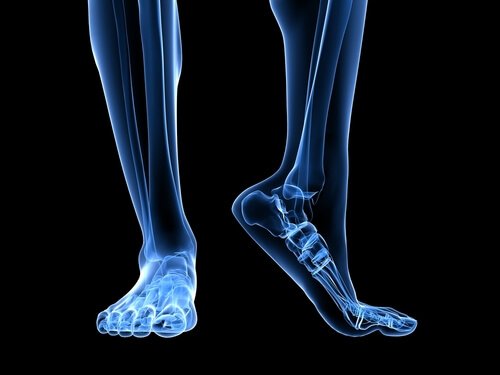

Fodens anatomi

Der er flere anatomiske strukturer, som spiller en rolle i enhver overbelastning af plantar fascia.

Akillessenen er en sene, som forbinder gastrocnemius musklerne, bedre kendt som lægmusklerne, og soleus musklerne med hælen. En sammentrækning af akillessenen udløser en øgning af presset på hælen, med den resulterende øgning af tryk på plantar fascia.

En anden faktor at have i baghovedet omkring den anatomiske struktur er fodens strækning, eller med andre ord, hvordan foden rammer jorden. Flade fødder eller fødder med tendens til at overpronere strækker plantar fascia mere, dermed øger det risikoen for brud på grund af det ekstra tryk på vævet.